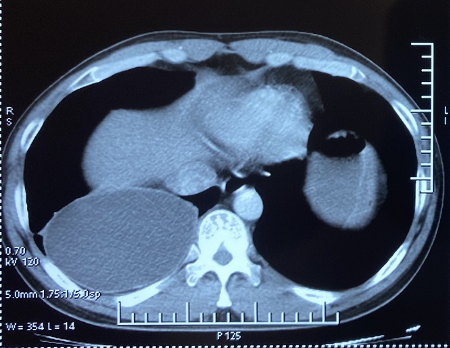

Tổn thương trên phim cắt lớp vi tính lồng ngực của bệnh nhân. (Ảnh: PV/Vietnam+)

Sau khi khám, kết quả chụp phim lồng ngực cho thấy có tổn thương dạng nang thùy dưới phổi phải kích thước 12x9x8cm. Bệnh nhân được chỉ định phẫu thuật cắt nang dịch.

Các bác sỹ đã tiến hành phẫu thuật nội soi lồng ngực cắt nang dịch cho bệnh nhân. Tổn thương trong mổ là một nang dịch kích thước lớn, thành dày, dịch nang trong, bên trong có chứa các đầu sán nằm ở thùy dưới phổi phải. Bệnh phẩm được gửi soi tươi xác định ấu trùng sán dây chó. Sau mổ bệnh nhân diễn biến ổn định, hồi phục tốt.